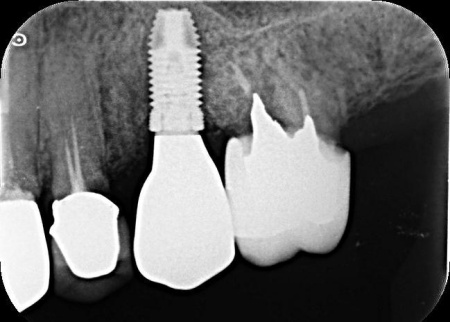

後日、インプラントが顎の骨にしっかりと結合したため、被せ物を作製します。

完成した被せ物を装着し、噛み合わせや使用感に問題がないことを確認して治療を終了しています。